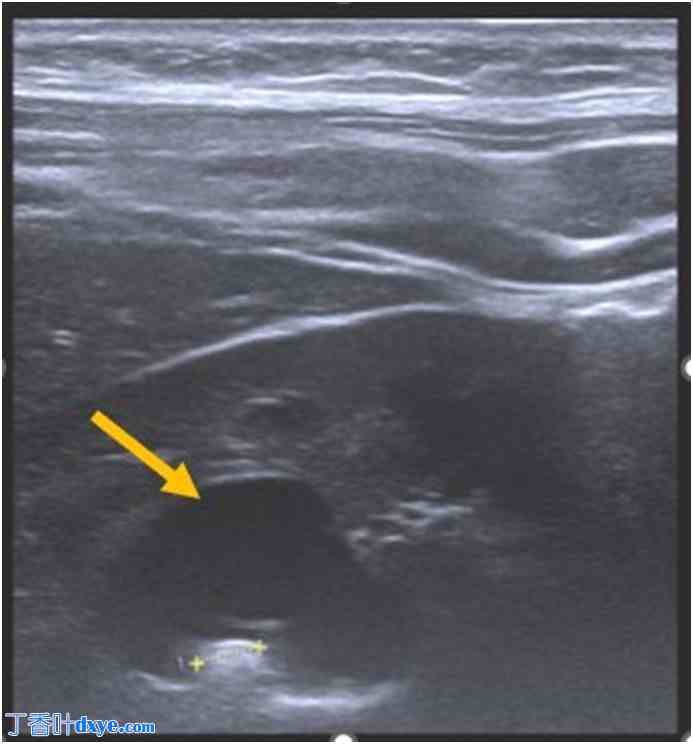

图 2.

(A) 横断面 CTU 扫描显示胆总管内有一小块下垂性结石(箭头)。(B) 冠状位增强 CTU 扫描显示胆盏中部有一处胆总管。